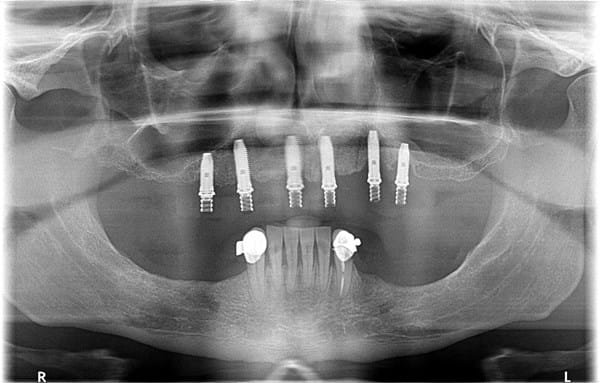

Salud dentalMedicina deseo1802 el 13 feb. 15 Duda sobre infección en implante dental Hola me gustaría saber si tengo infección en algún implante dentalPongo ortopantografia. Seguir Siguiendo Dejar de seguir